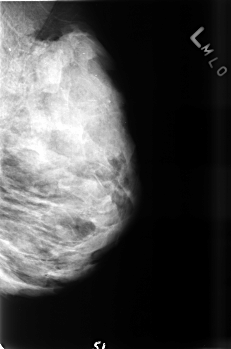

B_3469_1.LEFT_MLO

LEFT_MLO LINES 4536 PIXELS_PER_LINE 3000 BITS_PER_PIXEL 12 RESOLUTION 50 NON_OVERLAY